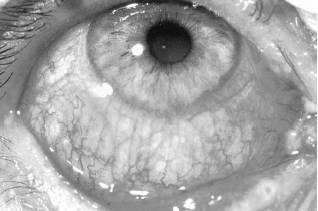

A20-year-old female presents to the office complaining that her right eye has been itchy and watery. The patient reports that the onset was abrupt. The patient is noted to be afebrile with normal vital signs. Examination discloses a red eye with watery discharge. Minimal preauricular adenopathy is also found on examination. Tonometry is normal. Profuse tearing is noted. Which of the following is the most likely diagnosis?

Viral (follicular) conjunctivitis most often presents with minimal discharge and itching as compared to the moderate-to-profuse discharge of bacterial conjunctivitis. While mild pain and photophobia may be noted in viral, bacterial, fungal, and allergic conjunctivitis, preauricular adenopathy is common in viral and fungal conjunctivitis only. Allergic conjunctivitis presents with minimal discharge and marked itching. The patient's young age and normal eye pressure (tonometry) helps to rule out glaucoma.